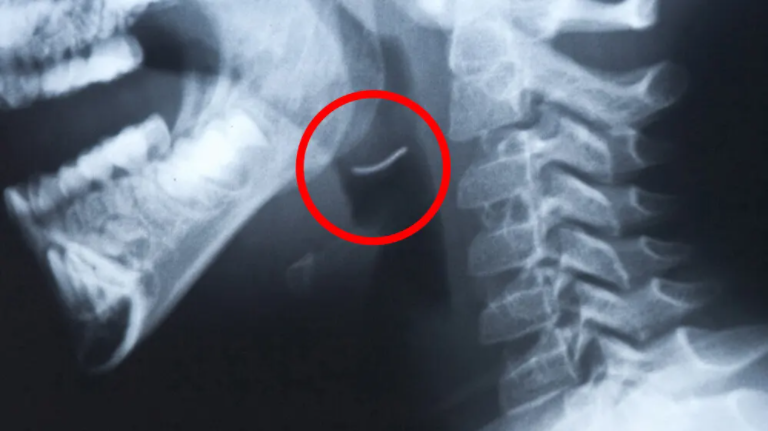

Every year on the news we hear about some poor unsuspecting person trying to enjoy a grilled meal, only to end up at the hospital with a GRILL BRUSH BRISTLE lodged in their throat. Not only is this SUPER painful, but it also usually requires surgery and will DEFINITELY ruin your meal.

We got this picture from a blog by our friends at Grill Rescue, another great grill brush alternative.